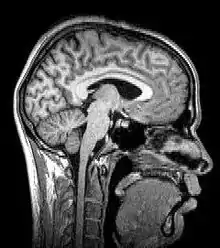

![]() Para-sagittal MRI of the head in a patient with benign familial macrocephaly. | |